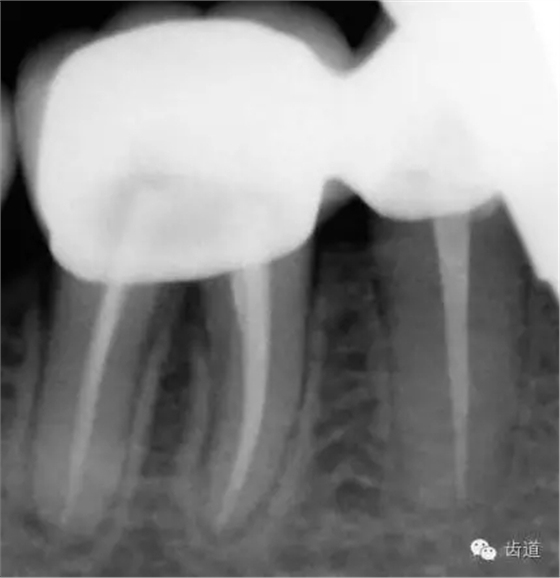

6、45,46,47牙片

5、34冠修復(fù),45,46聯(lián)冠修復(fù)(2013年10月)

6、26,27,47種植修復(fù)(2014年1月)